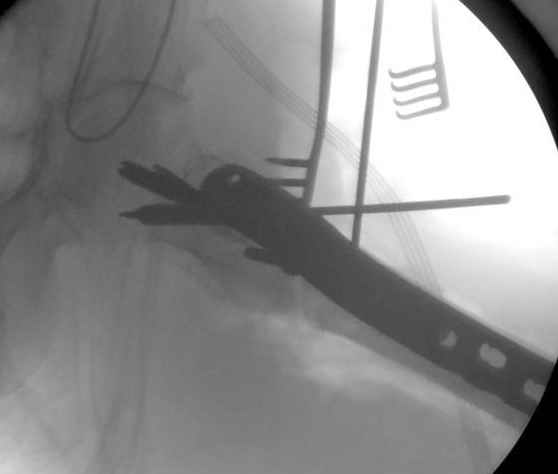

Применили проксимальную Synthes Locking plate, из-за множественных фрагментов посчитали более приемлемым в этом случае (клиника университетская, резиденты должны имет возможность созерцать разные варианты остеосинтеза).

Также старался минимизировать доступ на уровне перелома с субвастус доступом, диафиз фиксирован перкутанно, не стали гонятся за малым вертелом, как смог зафиксировал.

Перелом из четырех фрагментов, не стабильный (лекция Michael R. Baumgaertner, http://www.hwbf.org/ota/bfc/baumg/exp.htm), нужна стабильная фиксация.

Фиксация таких нестабильных чрезвертельных и reverse obliquity субтрохантерик переломов всегда была сложной задачей и ранее использовали Blade Plate. Но многие локальные общие ортопеды, к которым, в основном поступают такие больные, имели трудности с применением импланта, где необходимо было точная калькуляция по введению Blade и поэтому Synthes разработал Proximal Locking plate как альтернативу, где три проксимальные шурупа в разных направлениях создают концепцию угловой стабильности Blade Plate.